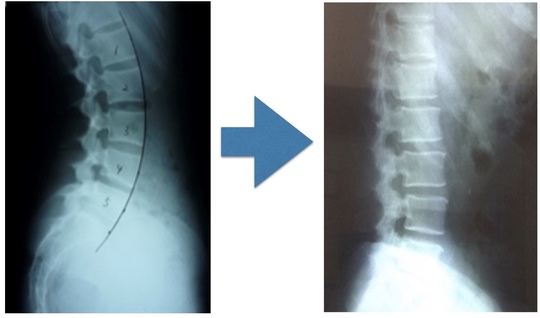

腰が反っていることで、腰・骨盤・股関節の一緒のうごきに制限がかかります。

この腰椎・骨盤・股関節の連動した動きを作る。

腰が反っているなら、反り腰を修正しなければなりませんし、連動した動きを作らなければなりません。